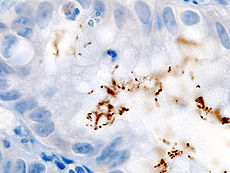

Colonization with H. pylori is not a disease in and of itself but a condition associated with a number of disorders of the upper gastrointestinal tract. Testing for H. pylori is recommended if there is peptic ulcer disease, low grade gastric MALT lymphoma, after endoscopic resection of early gastric cancer, if there are first degree relatives with gastric cancer, and in certain cases of dyspepsia, not routinely. Several ways of testing exist. One can test noninvasively for H. pylori infection with a blood antibody test, stool antigen test, or with the carbon urea breath test (in which the patient drinks 14C—or 13C-labelled urea, which the bacterium metabolizes, producing labelled carbon dioxide that can be detected in the breath). However, the most reliable method for detecting H. pylori infection is a biopsy check during endoscopy with a rapid urease test, histological examination, and microbial culture. There is also a urine ELISA test with a 96% sensitivity and 79% specificity. None of the test methods is completely failsafe. Even biopsy is dependent on the location of the biopsy. Blood antibody tests, for example, range from 76% to 84% sensitivity. Some drugs can affect H. pylori urease activity and give false negatives with the urea-based tests.